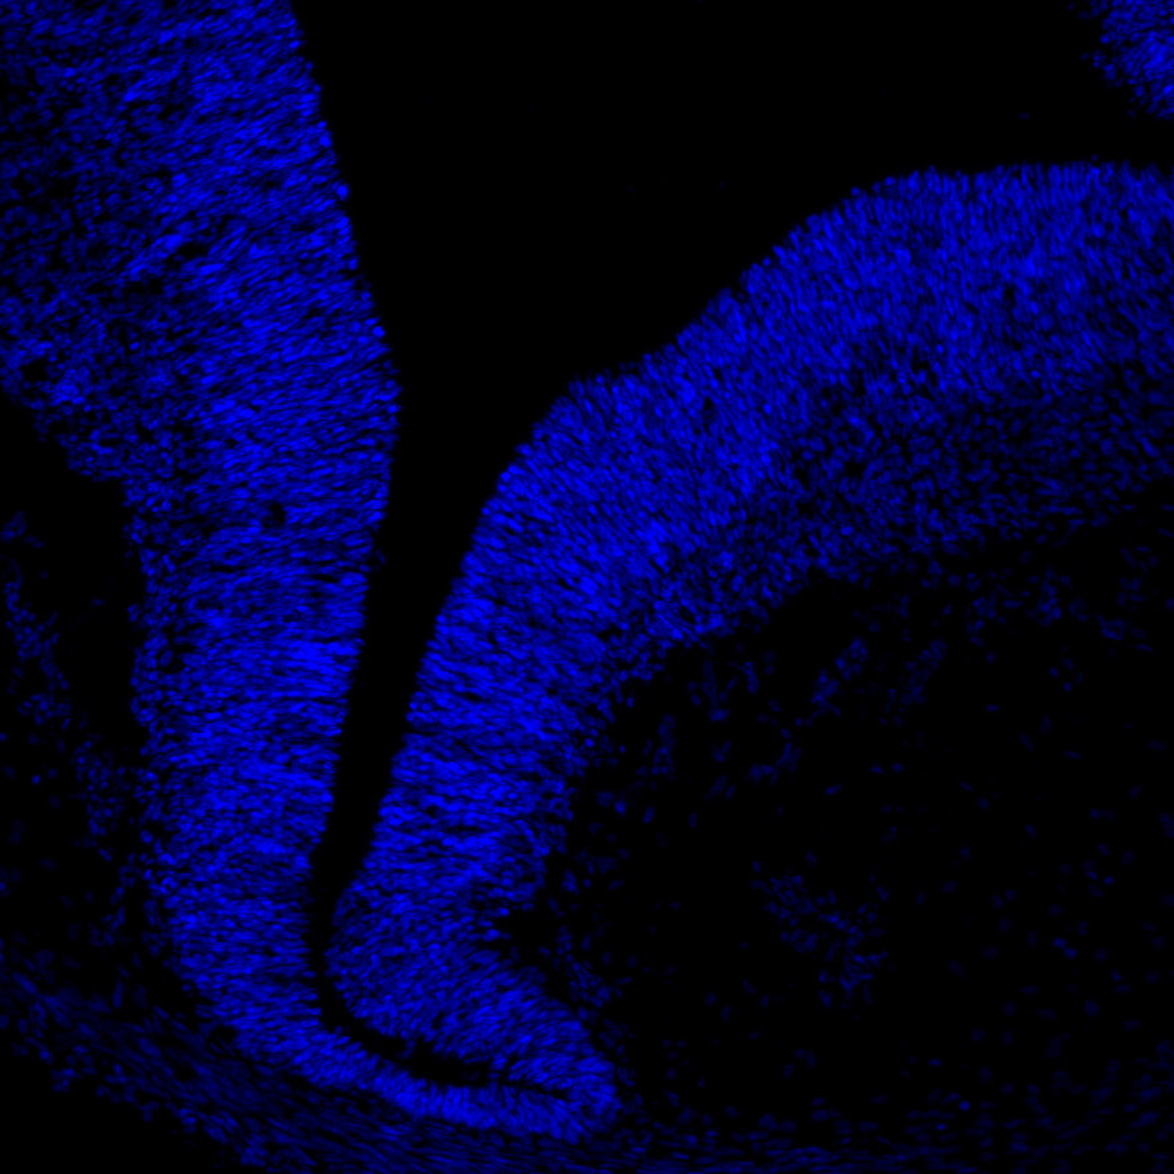

DAPI

11PCW human midbrain